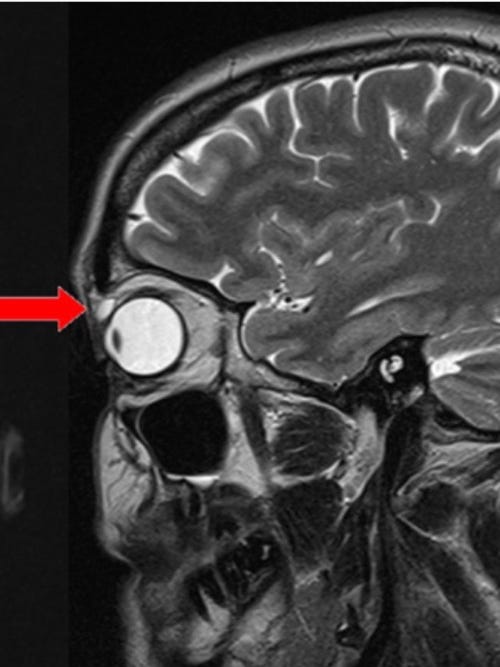

ولكن بعد ستة أشهر، تورم الجفن نفسه، ونمت كتلة عليه وأصبحت مؤلمة عند لمسها. ذهبت كترينا إلى طبيب الأسرة، الذي أحالها إلى طبيب عيون للتحقيق في المشكلة. كانت بصرها جيدًا، وبدا أن كلتا عينيها طبيعيتين باستثناء التورم. لم يكن هناك إفرازات غريبة أو حساسية أو احمرار. ومع ذلك، تمكن الأطباء من الشعور بتكتل صغير تحت جلد الجفن العلوي الأيسر، وقرروا إجراء فحص بالرنين المغناطيسي لمعرفة ماهيته. أظهر الفحص أن الكتلة كانت لها خصائص كيس واضح . كان طوله حوالي ثمانية مللي مترات، وتقع فوق عين المريضة اليسرى مباشرة.